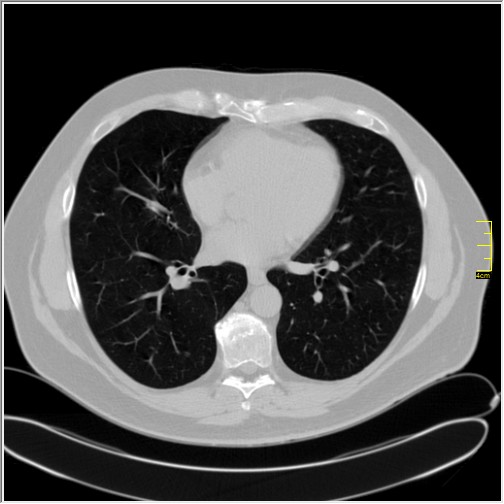

Pacijent prvi put dolazi 3 dana nakon pojave simptoma a dva dana nakon pozitivnog testa. Ima temperaturu koja tek prelazi 37. Ne kašlje, testirao se kao kontakt. Oseća mirise i ukuse. Po laboratoriji pulmolog koji ga je pregledao misli da je moguće da se radi o nekom novom soju. Nije vakcinisan. Nije ni antivakcinaš. Jednostavno je mislio da sačeka.

Severity score 0/25. Najdraže mi je kada vidim to.